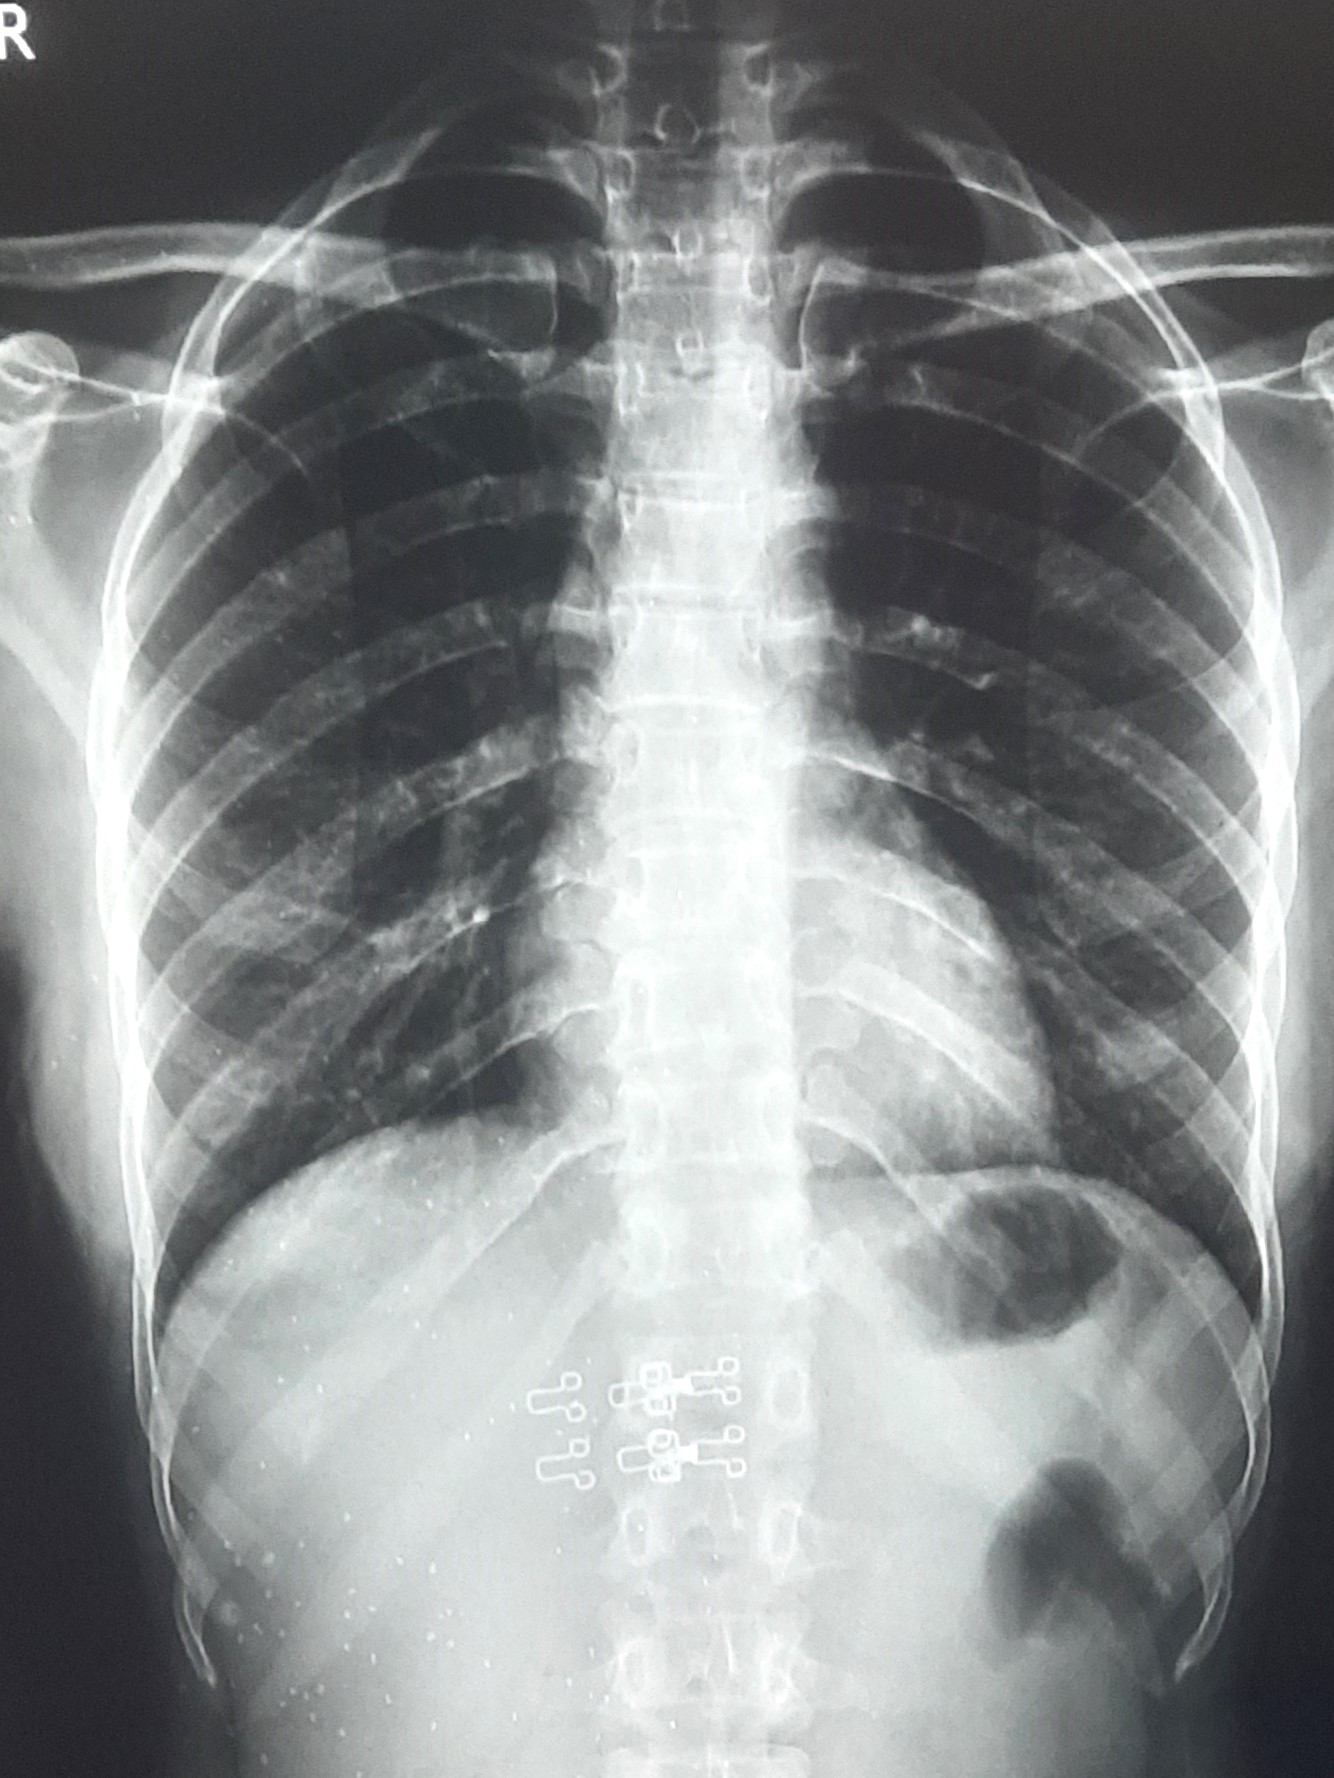

| 271 | IGGMC, Nagpur, Nagpur | P2 | 29-4201 | Abddul Qayyam | Consent taken on Paper | 75 Yrs. |

Provisional Diag : Upper Respiratory Tract Infection

Final Diag : FIBROSIS |

Non-TB Case (Confirmed) | RETICULAR OPACITIES NOTED IN PREDOMINANTLY IN UPPER ZONE OF RIGHT LUNG PARENCHYMA | Abnormality visible on x-ray |